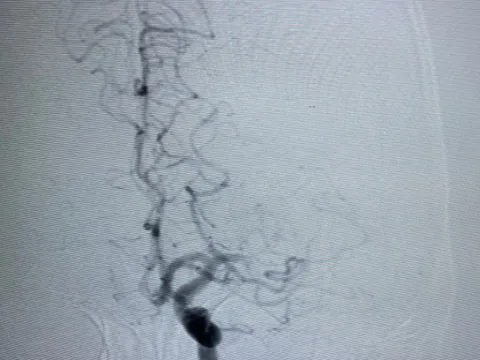

Tp.HCM: Người phụ nữ trẻ đột quỵ được cấp cứu kịp thời

Dù có nếp sống lành mạnh, hàng ngày dậy từ 6h sáng để đi làm nhưng người phụ nữ trẻ vẫn bị đột quỵ, mất ý thức và phải nhập viện cấp cứu kịp thời.